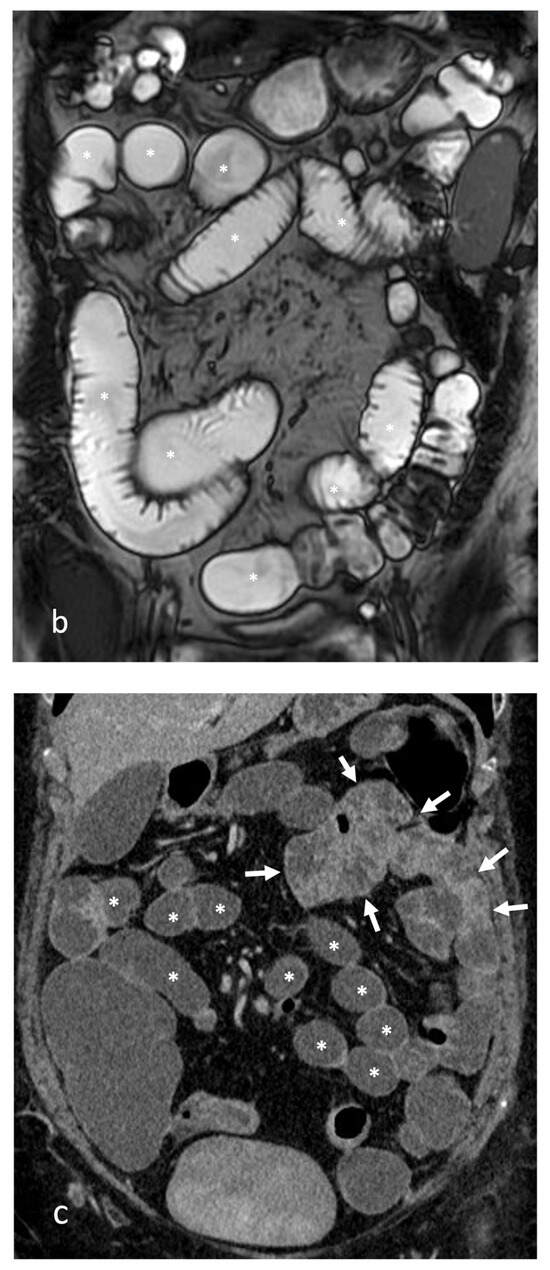

- A normal bowel loop caliber ranges between 2 and 2.5 cm. A bowel lumen is dilated when it has a maximum diameter greater than 2.5–3 cm. The dilation is mild when the upstream lumen is dilated up to 4 cm and severe when it is more than 4 cm (Figure 3) [24]. Pre-stenotic bowel dilatation should always be checked, as it is a sign related to bowel obstruction. Moderate to severe stenosis was determined via double-contrast imaging (conventional barium study) with a sufficient amount of injected air, and stenosis was defined as stenosis in which the lumen was less than one half that of neighboring healthy intestine [25].